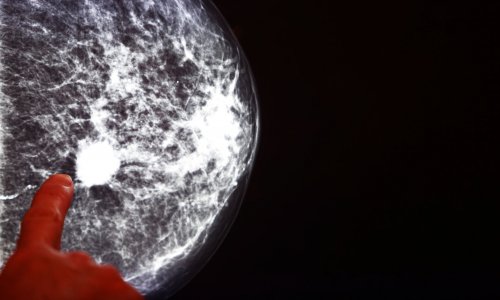

The incidence of colorectal cancer is rising among younger individuals, sometimes as early as their thirties. The research also shows the challenge of late diagnoses and calls for increased awareness.